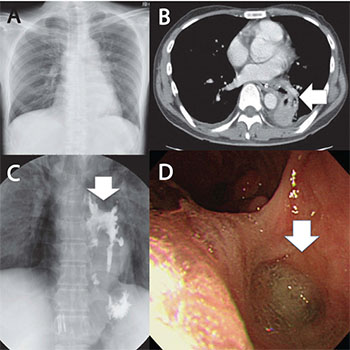

A 47-year-old man was admitted to our emergency department with complaints of fever, cough, and dysphagia with liquid ingestion. Information from the hospital from which he was transported indicated that esophageal tissue biopsy disclosed no evidence of malignancy, cytomegalovirus (CMV), or herpes simplex virus. Tuberculosis was not identified by interferon-gamma release assays test and polymerase chain reaction from the sputum. Findings from his general examination on arrival were as follows; heart rate 95 beats per minutes, blood pressure 97/66 mmHg, respiratory rate 16 breaths per minute, oxygen saturation 100% with 2L oxygen, body temperature 36.60 C, Glasgow Coma Scale score E4V5M6. Laboratory examination results were as follows: white blood cells 8700/μ,, hemoglobin 10.4g/dl, C-reactive protein 14.3mg/dl (Table 1). Anti-human immunodeficiency virus (HIV) test was negative. His chest radiography showed an abnormal shadow in the left lower field, suggesting pneumonia (Figure 1A). Chest computed tomography revealed a fistula running from the middle esophagus to the left lower bronchus, with pneumonia and atelectasis in the left lower lobe (Figure 1B). Contrast radiography of the upper gastrointestinal tract showed a barium outline of the esophagus, fistulous tract, and the left lower lobe bronchus (Figure 1C). To detect the cause of the fistula, gastrointestinal fiberscopy (GIF) was performed. Multiple longitudinal ulcers and fistulas were recognized (Figure 1D). No malignant or inflammatory tissues were recognized from GIF or previous hospital findings. Considering the above findings, we diagnosed the patient with idiopathic BEF with unknown origin. He was transferred to the surgery department located next to our facility.

Figure 1: A: Abnormal shadow in the left lower field on chest roentgen on arrival; B: Arrow head revealed a fistula running from the middle esophagus to the left lower bronchus, with pneumonia and atelectasis in the left lower lobe on computed tomography; C: Arrow head revealed a barium outline of the esophagus, fistulous tract, and the left lower lobe bronchus on contrast radiography of the upper gastrointestinal tract; D: Arrow head demonstrated multiple longitudinal ulcers and fistulas on gastrointestinal fiberscopy.